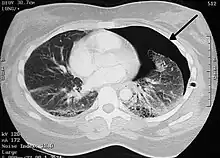

Les maladies ou les évènements préjudiciables qui peuvent affecter la respiration sont nombreux. La médecine définit les maladies respiratoires comme celles qui endommagent ou perturbent le fonctionnement des organes de la ventilation (l'appareil respiratoire au sens anatomique). La pneumologie traite ainsi de tous les troubles qui concernent les poumons, la plèvre, les bronches ou la trachée.

Les œdèmes du poumon résultent d'une accumulation de liquide dans les alvéoles ou les espaces interstitiels. Ils peuvent être d'origine cardiaque (œdème aigu pulmonaire cardiogénique), lésionnelle (œdème pulmonaire lésionnel) ou causés par l'altitude (œdème pulmonaire de haute altitude).

Les pneumonies sont des inflammations infectieuses des poumons, avec accumulation de pus ou de sécrétions. Elles sont causées par des bactéries (Streptococcus pneumoniae, Haemophilus influenzae, Legionella pneumophila, Mycoplasma pneumoniae, etc.) ou par des virus (de la grippe A, de la rougeole, de la Covid-19, etc.).

Une atélectasie désigne la rétraction d'alvéoles pulmonaires, voire l'effondrement d'un lobe ou du poumon entier. Dans le premier cas, c'est le blocage d'une bronche qui produit l'affaissement de la partie privée d'air. Dans le second cas, c'est l'entrée d'air dans la cavité pleurale qui provoque un pneumothorax : le poumon se décolle de la cage thoracique.